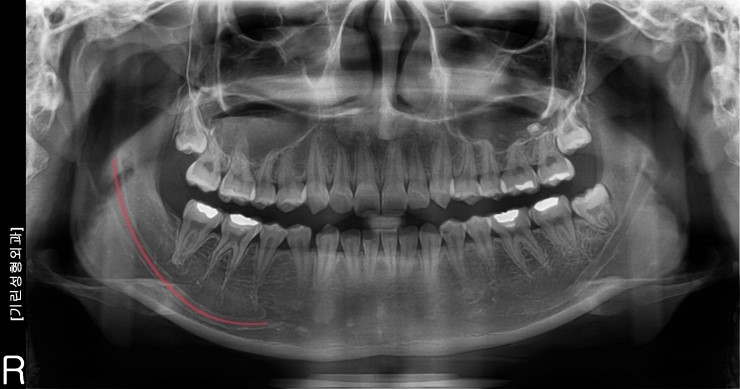

아래 파노라마사진에서 붉은선으로 표시된 부분이 바로 신경선이 지나가는 길입니다.

신경선은 턱의 양쪽으로 자리잡고 있는데 신경선의 위치와 사각턱수술의 절골범위가 관련이 있습니다.

사각턱수술 시 나타날 수 있는 부작용증상중 하나가 신경선의 손상인데

신경선이 아래로 내려와 있는 경우 신경을 피해서 절골해야 하기 때문에

절골할 수 있는 범위는 그만큼 줄어듭니다.

신경의 손상은 위 사진처럼 파노라마, CT촬영으로 판단이 가능하기 때문에 사각턱수술 후 이상증상이 나타난다면 촬영을 통해 정확한 판단을 하는것이 좋습니다.